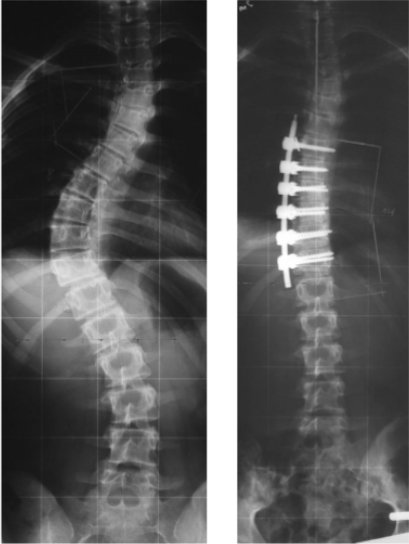

45 jährige Frau mit alter idiopathischer Skoliose

Dorsale Skoliose-Operation

Der Großteil der Skoliosen wird heute von hinten, also dorsal, operiert. Dank moderner Systeme sind ähnlich kurze Operationsstrecken möglich. Patientinnen und Patienten liegen während des Eingriffs auf dem Bauch und die Wirbelsäule wird durch einen mittigen geraden Schnitt freigelegt.

Anschließend werden Schrauben in den Wirbelköpern verankert, an denen die einzelnen Wirbel dann ausgerichtet werden können. Durch neue Techniken mit Schrauben, die auch eine  Drehung (Derotation) der einzelnen Wirbelkörper erlauben, können mittlerweile ähnlich gute Ergebnisse, wie mit der Skoliose-OP von vorn, erzielt werden. Desweitern können von hinten zusätzlich noch die Wirbelgelenke gelöst werden, um die Wirbelsäule flexibler zu machen. Der Rippenbuckel wird durch Osteotomien der Rippen korrigiert und Schmerzkatheter werden entsprechend eingelegt.

Thorakolumbale Krümmung Th 10 bis L3 von dorsal

Thorakale Krümmung Th 3 bis 12 von dorsal